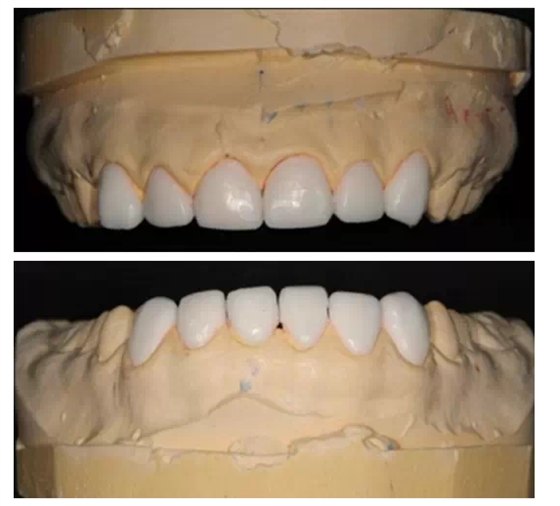

這時醫(yī)生已經(jīng)拿到技師做好的美學(xué)蠟型,可以讓患者看到與之前最直觀的對比。

如同買房子,美學(xué)蠟型當于沙盤,沙盤可以制作的無比精良,但是僅僅看到沙盤是不夠的,我們必須要看到樣板間,準確的知道這套房子最終會建成什么樣子,這就是我經(jīng)常和大家提到的Mock up(樹脂罩面)。

把技師做好的美學(xué)蠟型,用臨時冠材料準確的復(fù)制到患者的口內(nèi),讓患者最直接的看到修復(fù)后的效果。如果需要進行少量的牙體預(yù)備,一定要征求患者同意后再進行。